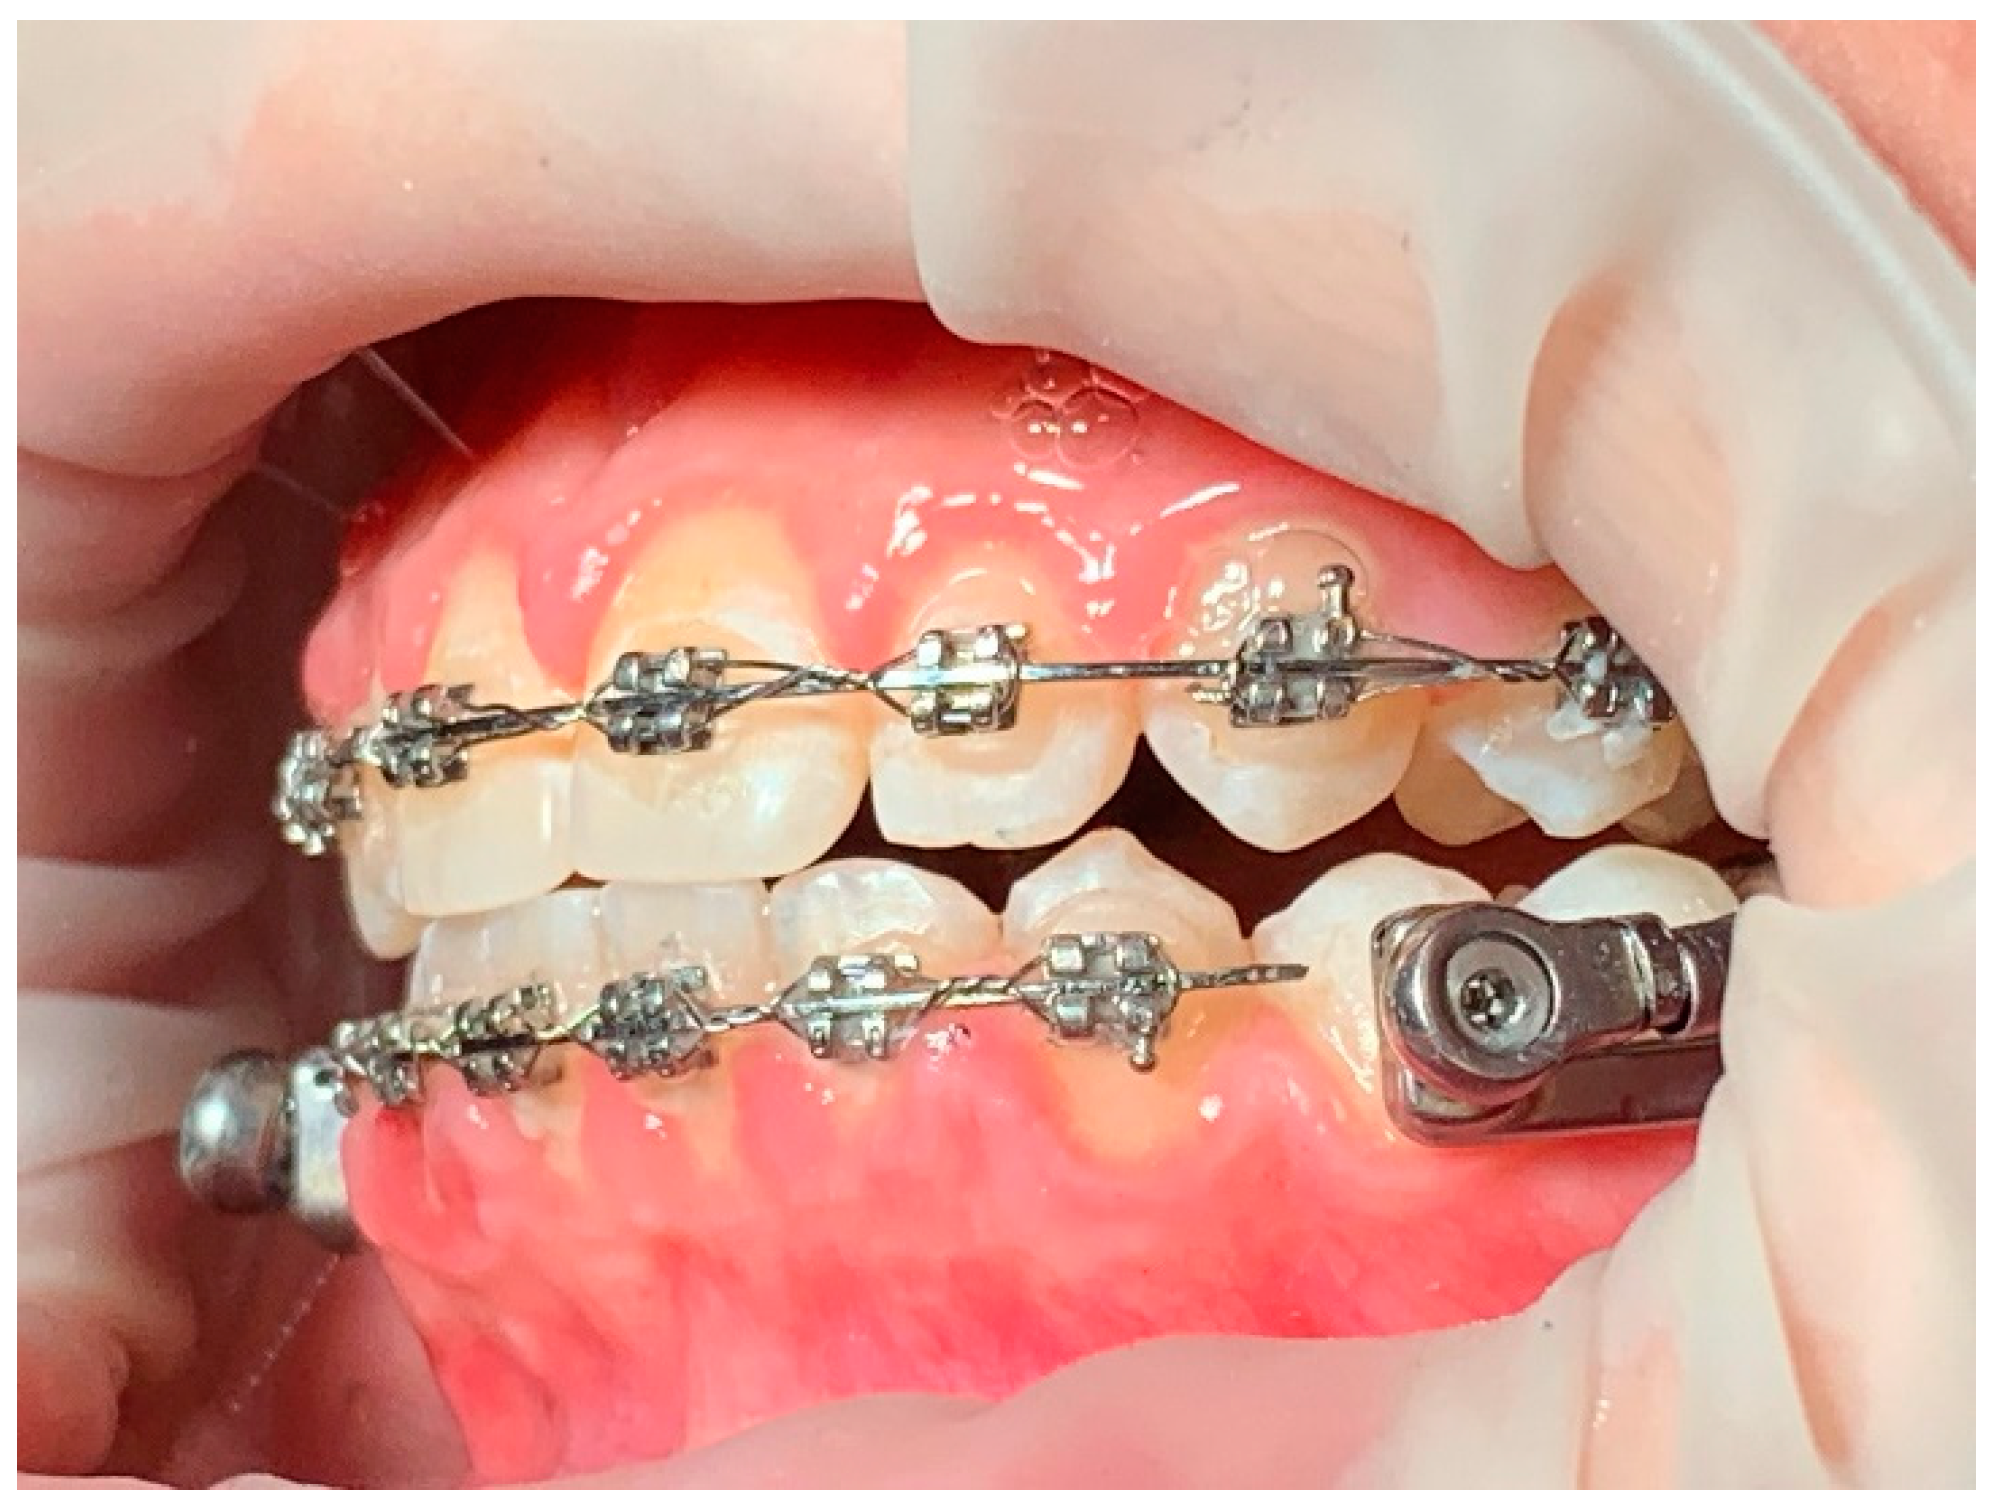

The following is a case in which the simplified model and the sequence of clinical phases were used. In our clinical practice, the treatment begins with a phase of alignment and leveling of the arches, elimination of the excessive pro-inclination of the incisors (for example in the case of diastemas as visible in photo (

Figure 2a,b), coordination of the arches through coordinated final steel arches; coordination is checked clinically by manually guiding the patient and asking for the positioning of the protruding mandible with contact of the incisal edges with approximately 2 mm of overjet.

At this point of the treatment, the simplified Herbst device is applied: the dental arches remain spaced apart for a period of 7 days from the application of the device in the mouth. In this adaptation period, initially only the incisors of the upper arch make contact with those of the lower arch, in a ratio of 1mm of overjet (

Figure 3). The re-maining dental elements of the frontal group are supported by a rectangular sectional wire. Through the procedure of preparing the arches with MBA, phase with the Herbst device, and finalizing the therapy again with MBA, the treatment times in this clinical case were reduced in the phase with Herbst to 5 months compared to the 6-9 expected. This can be an interesting aspect both for less permanence of the device in the mouth which has a specific size, and for greater cleanability of the oral cavity and patient comfort.